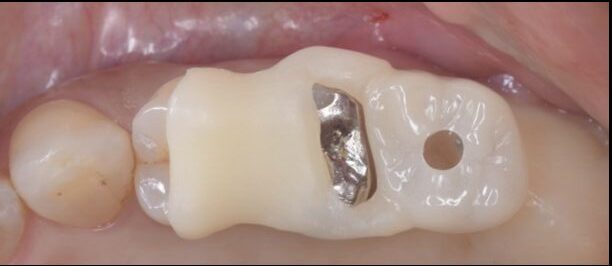

Before

左上の大臼歯が破折しており、保存が不可で抜歯を行い2ヶ月治癒を待ちました。